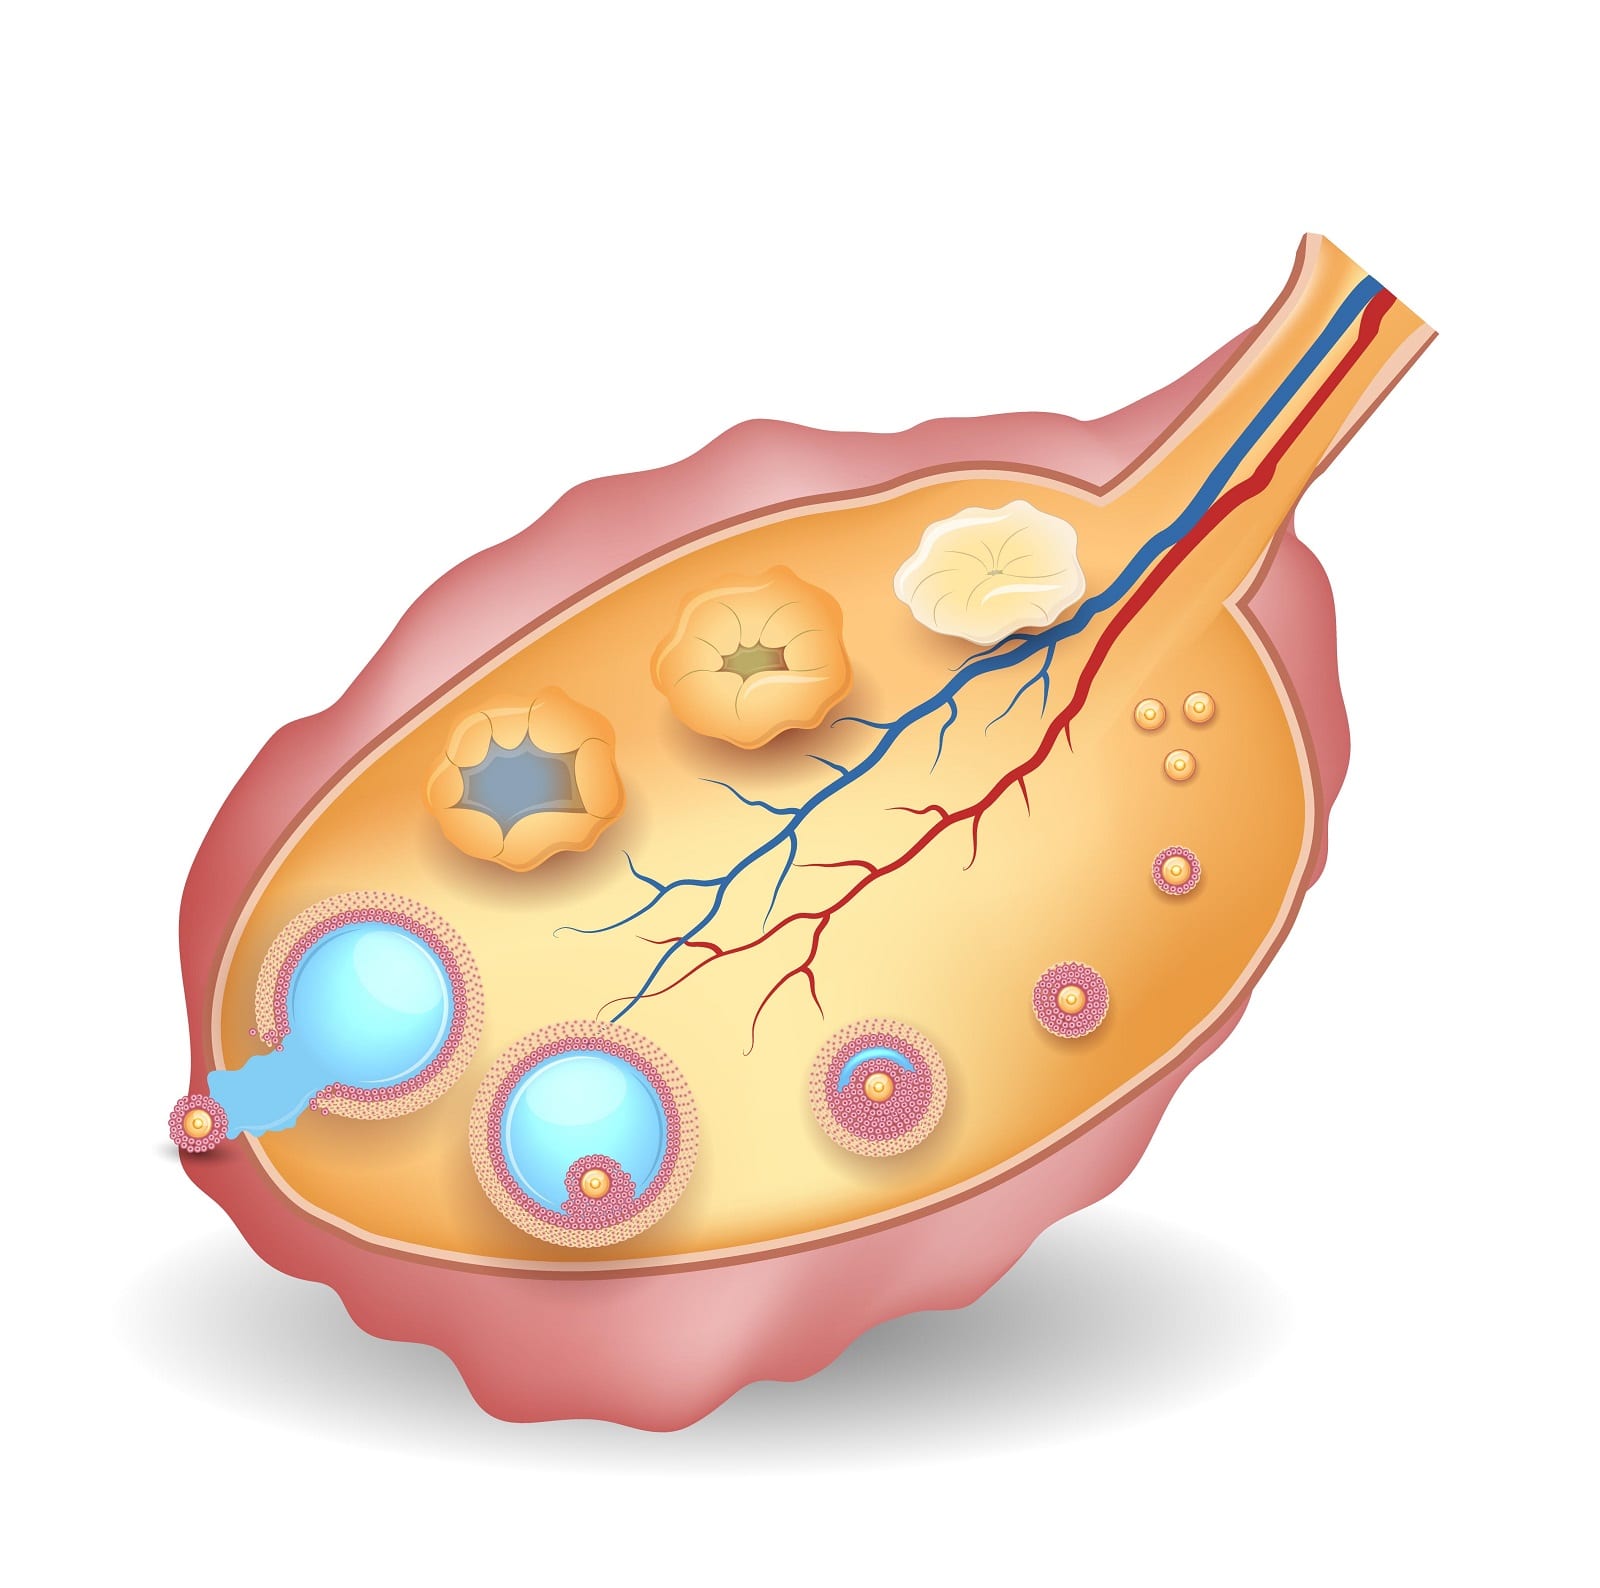

Созревание фолликула в яичнике: этапы и процессы